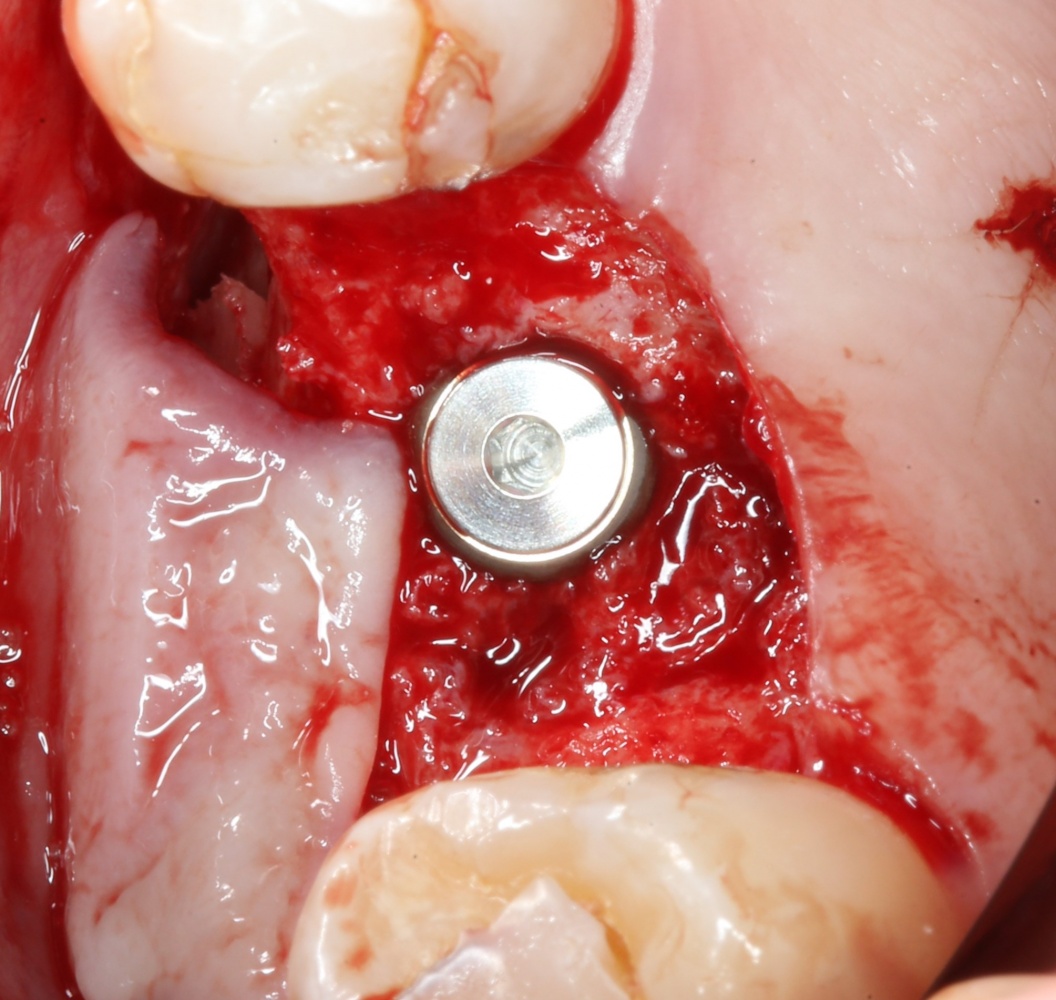

Кортикальная фреза погружается строго до отметки (см выше). В нашем клиническом случае (с синуслифтингом) это особенно важно, чтобы имплантат не улетел в субантральное пространство. Таким образом получаем лунку, полностью конгруэнтную будущему имплантату. Это очень-очень важно:

Если лунка подготовлена правильно, то имплантат проваливается в неё почти полностью: